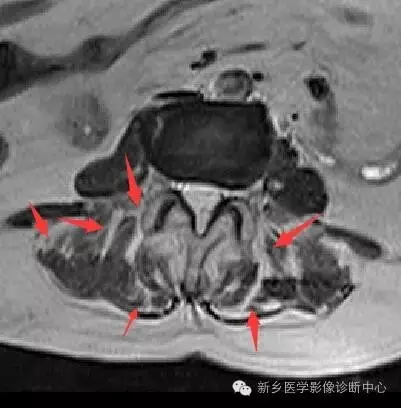

正常的肌肉在 MRI 上表現為形態飽滿、 輪廓清晰平滑的均質低訊號。男性的腰背肌厚度通常比女性要飽滿,肌纖維也要粗大。

長時間的腰背部肌肉疲勞狀態會導致其形態學發生改變,表現在肌肉體積的萎縮,肌肉邊緣輪廓的模糊和凹陷,訊號呈現出不均質改變, 這點在橫軸位的脂肪壓制像上體現得尤為明顯。

觀察肌間隙的脂肪浸潤也是衡量腰肌勞損的指標之一。脂肪浸潤通常伴隨有肌間隙的擴大,在MRI上呈現出三級訊號 ,Ⅰ度表現為肌間隙顯示不清或僅能顯示線狀、 點狀間隙擴大; Ⅱ度顯示為多灶性間隙擴大伴脂肪訊號; Ⅲ度浸潤表現為肌間隙呈羽毛狀或網格狀增寬,以上間隙的擴大和脂肪的浸潤是相伴相生的,也就是說擴大的肌間隙裡通常由脂肪填充。

腰肌勞損的特徵性表現是肌筋膜炎。也就是位於肌間隙和肌骨間隙的組織液滲出, 組織粘連和積液,腰背部肌肉和筋膜的水腫訊號是判斷腰肌勞損的重要標誌之一,且淺筋膜的病變發現率要高於深筋膜。具體表現為腰背部皮下、 腰肌及筋膜下線狀、 條狀或片狀的長 T1長T2,FS-T2WI高訊號。